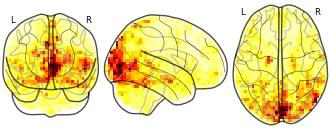

Movie clips: importance map OD 3 Happiness

niftiUpdated Jan 9, 2018+ more versions Share

EmailClick to copy linkLink copied Cite(2018). Movie clips: importance map OD 3 Happiness [Dataset]. http://identifiers.org/neurovault.image:58832niftiAvailable download formatsUnique identifierhttps://identifiers.org/neurovault.image:58832Dataset updatedJan 9, 2018License

Cite(2018). Movie clips: importance map OD 3 Happiness [Dataset]. http://identifiers.org/neurovault.image:58832niftiAvailable download formatsUnique identifierhttps://identifiers.org/neurovault.image:58832Dataset updatedJan 9, 2018LicenseCC0 1.0 Universal Public Domain Dedicationhttps://creativecommons.org/publicdomain/zero/1.0/

License information was derived automaticallyDescription - m